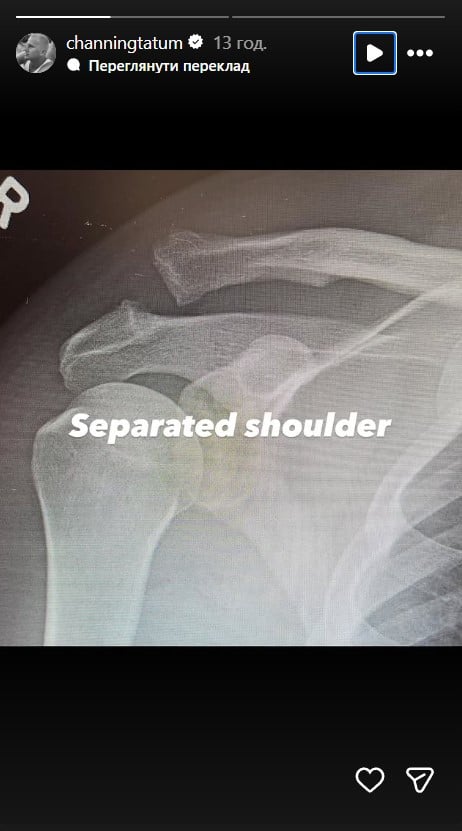

Пізніше артист опублікував два рентгенівські знімки - до і після операції. На одному можна розгледіти вивих плеча в області ключиці, на іншому - з'єднаний гвинтом суглоб.